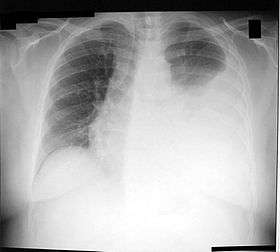

![]() Chest X-ray showing a left-sided pleural effusion (right side of image). This can be treated with thoracentesis. | |